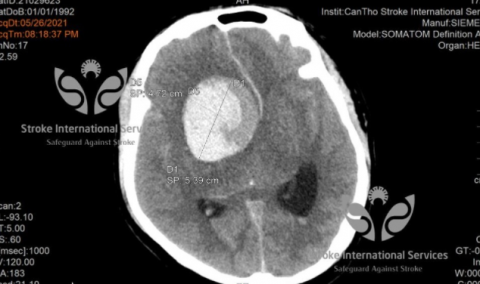

TS Trần Chí Cường – Giám đốc BV đa khoa quốc tế Cần Thơ chia sẻ về một trường hợp bệnh nhân nam 29 tuổi được đưa vào bệnh viện cấp cứu trong tình trạng đau đầu dữ dội, hôn mê sâu. Người nhà cho biết, trước đó, bệnh nhân đã bị đau đầu và đi khám uống thuốc nhưng không đỡ. Theo bác sĩ, bệnh nhân có một túi phình mạch máu não khổng lổ, kích thước lên tới 5cm (tương đương với kích thước của một quả chanh). Túi phình bị vỡ khiến bệnh nhân lâm vào nguy kịch.

Túi phình mạch máu của bệnh nhân có kích thước lên tới 5cm.